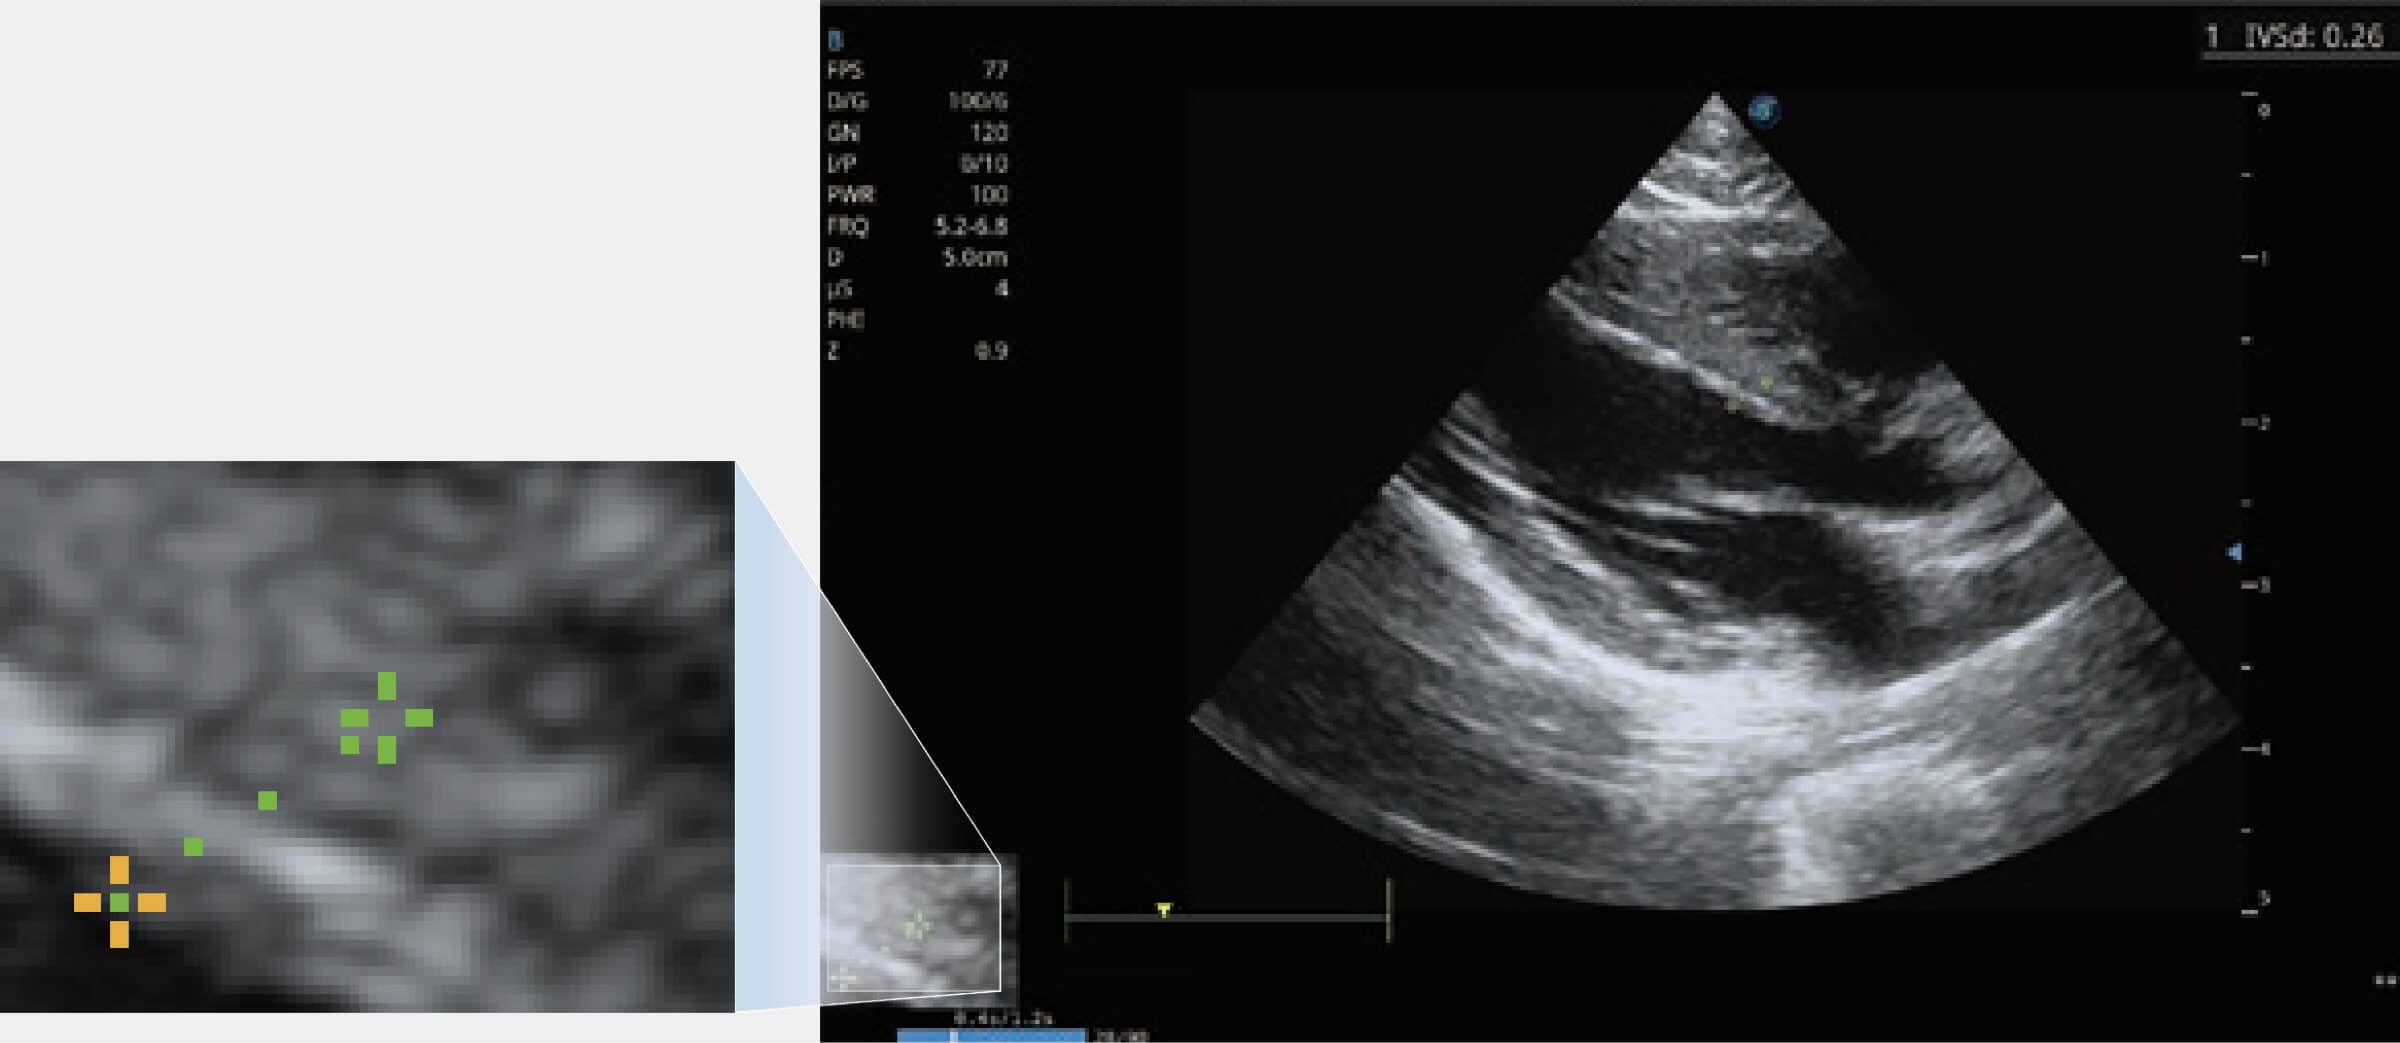

能夠基于左心室壁追蹤和辛普森法,自動計(jì)算射血分?jǐn)?shù),支持多個可移動點(diǎn)描跡,與手動測量相比,極大節(jié)省了動物醫(yī)生的時(shí)間和精力。

通過360度任意調(diào)節(jié)3條M型取樣線,在同一心動周期上觀察心臟不同位置的運(yùn)動曲線,得到準(zhǔn)確的心功能測量數(shù)據(jù),有效評估心肌運(yùn)動及左心室功能。

實(shí)時(shí)用顏色表示心肌組織運(yùn)動,觀察和定量組織的運(yùn)動情況,對快速檢測與評估心肌的灌注和活性、電傳導(dǎo)及心肌收縮和舒張功能等均能提供重要的診斷信息。